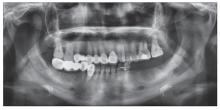

图 2

病例2术前曲面断层片 黑色箭头:左下颌管区域。"

病例2术后半年曲面断层片"